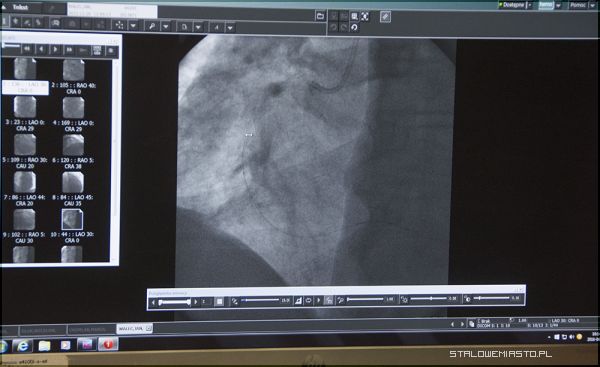

W stalowowolskim oddziale Kardiologii Inwazyjnej i Angiologii stosuje się takie metody leczenia jak: rotablacja, IVUS, FFR,TEE, ablacja. Jak rozwijał się oddział przez 10 lat?

- Na początku wykonywaliśmy głównie badania koronograficzne czy diagnostyczne, potem dołączyły zabiegi poszerzania tętnic wieńcowy, oczywiście u tych pacjentów, którzy się kwalifikują do poszerzania. Część pacjentów się nie kwalifikuje i musi być leczona kardiochirurgicznie i była odsyłana do ośrodków kardiochirurgicznych. Też nie wszystkie tętnice wieńcowe byliśmy w stanie poszerzać dlatego, że stopień zwężenia, stopień zaawansowania zmian w tętnicach wieńcowych może być bardzo różny. Zasadniczym i bardzo istotnym naszym osiągnięciem było to, że poprzez wyeliminowanie transportu pacjentów z zawałem serca do odległych ośrodków takich jak Rzeszów czy Kraków, skróciliśmy dystans i czas od początku dolegliwości do wdrożenia terapii, w którym zasadniczym zadaniem jest otwarcie tętnicy dozawałowej, czyli przywrócenie przepływu w tętnicy, poszerzenie tej tętnicy balonikiem i założenie stentu- takiej protezy metalowej, która zapobiega zapadaniu się światła naczynia- mówił podczas konferencji Łukasz Rzeszutko, dr n. med., specjalista chorób wewnętrznych, specjalista kardiolog, który brał już udział w pierwszych zabiegach wykonywanych w Stalowej Woli.

W stalowowolskiej placówce leczeni są również pacjenci ze stabilną chorobą wieńcową. Długotrwała choroba obrazuje się występowaniem zwapnień w tętnicach. O ile to uwapnienie nie jest duże, istnieje możliwość „przepchania” tętnicy balonem i wysokociśnieniowymi inflacjami (w tętnicy o średnicy między 2 a 4 mm używane jest ciśnienie 20-40 atmosfer! Dla porównania w kole są ok. 2 atmosfery). Czasem się zdarza, że wykonanie tego zabiegu jest niemożliwe. Wówczas stosuje się rotablację.

Jakie nowości pojawiły się w stalowowolskiej kardiologii? Po pierwsze: rotablacja – zabieg usuwający silnie uwapnione złogi miażdżycowe, które powodują zwężenia światła naczynia krwionośnego.

– Stosujemy ją wtedy, gdy u pacjenta nie da się rozszerzyć tętnicy za pomocą balonikowania. W tej sytuacji wprowadzamy do niej obrotowy bor – wirujący z prędkością nawet do 200 tys. obrotów na minutę, który rozbija blaszkę miażdżycową. Wcześniej musieliśmy odsyłać takich pacjentów do innych ośrodków, np. w Krakowie, a teraz możemy pomóc im sami– mówił w piątek Łukasz Rzeszutko.

Kardiolog opowiedział również o nowych metodach diagnozowania, stosowanych w Oddziale Kardiologii Inwazyjnej i Angiologii. Pierwsze to ultrasonografia wewnątrzwieńcowa, która jest jednym z najbardziej precyzyjnych narzędzi do oceniania wielkości światła tętnicy, a także budowy ściany naczynia krwionośnego. Drugie z nowoczesnych badań jakie zaczął ostatnio stosować stalowowolski szpital, to pomiar cząstkowej rezerwy przepływu. Polega ona na mierzeniu ciśnienia przed i za zmianą miażdżycową w tętnicy, umożliwiając lekarzom podjęcie decyzji o optymalnym sposobie jej leczenia.